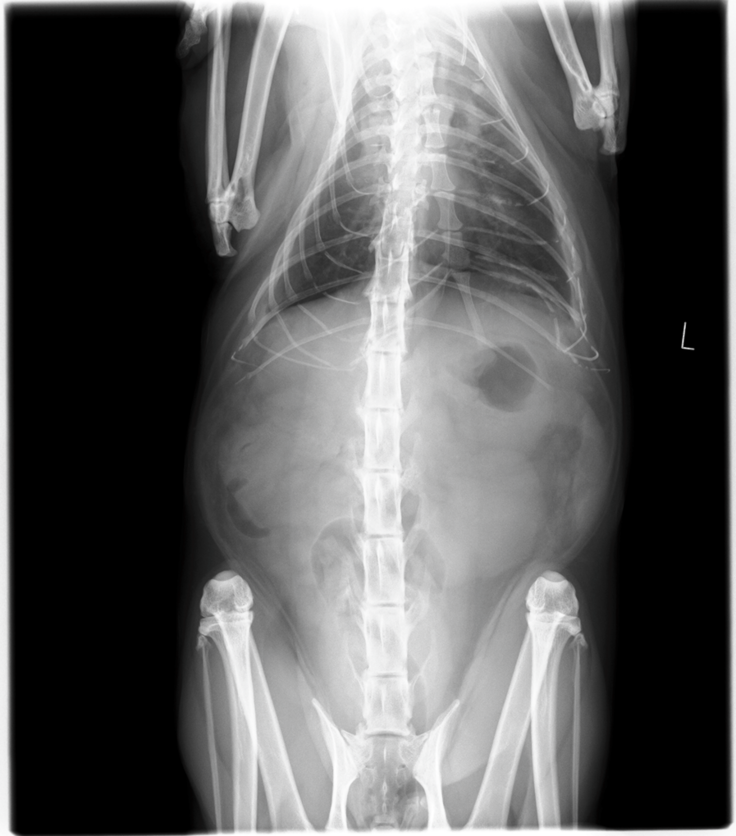

今年の1月頃から少しずつルートの元気が無くなり、体を撫でていると徐々に骨の感触が感じられれました。ルートはもともとふっくらしていたので年齢と共に瘦せてきたかなと思いましたが、やっぱり元気がないので病院で検査をすると、「胸部に水が溜まっていて早めに水を抜かないと生命に危険がある」との事でした。すぐに胸水を抜いてもらい、原因を探るために、より精密な検査が行える病院を紹介してもらいました。

獣医さんの診断でルートがリンパ腫、いわゆる”がん”である事を伝えられ状態はステージ3で、余命は1~3ヶ月であると告げられました。

↓超音波・X線検査

リンパ

腫は血液のがんで、外科的治療(摘出)ができないので以下の選択をすることになりました。